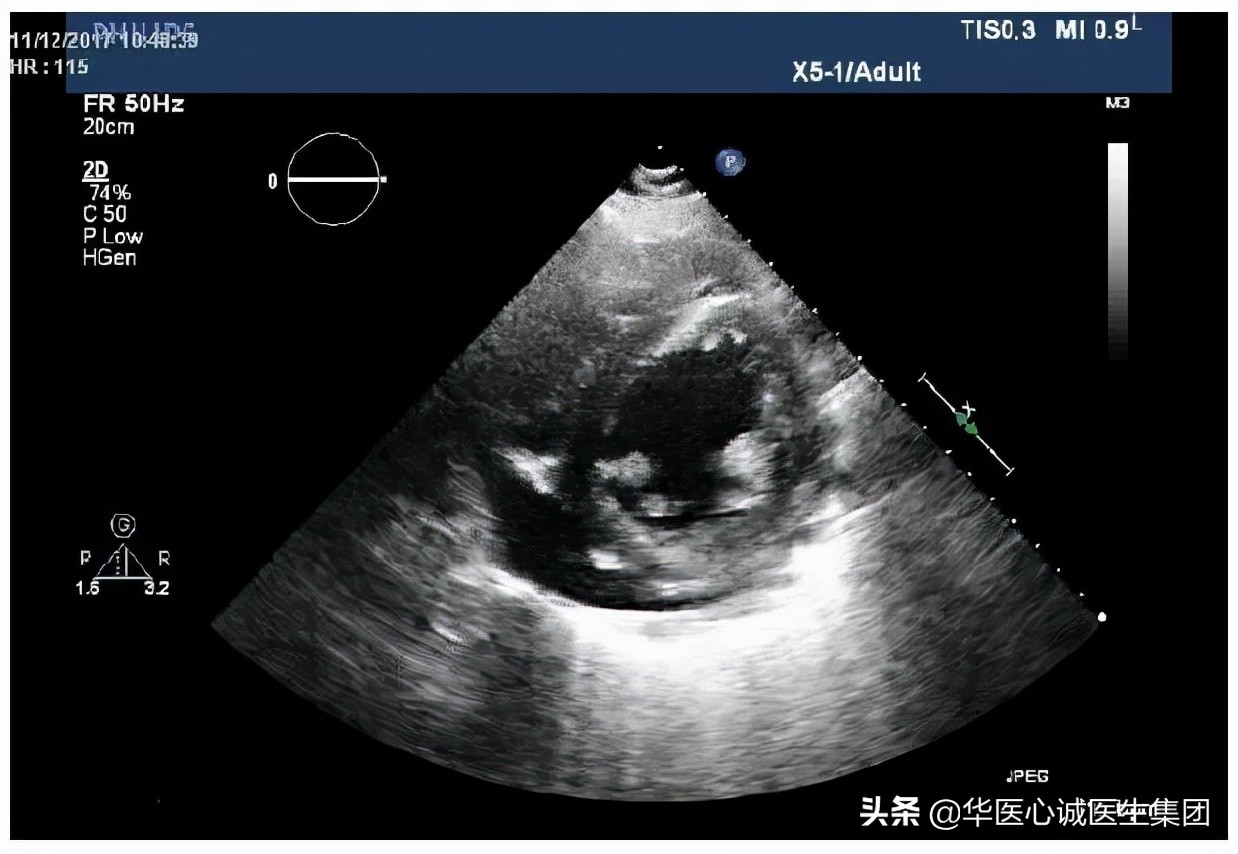

超声结果提示有心包积液,室壁增厚,约1.5cm。心腔扩大,左房、左室、右房均扩大,且收缩幅度下降。

- 左室短轴切面:可见心包积液,左室壁对称性增厚,室壁弥漫性运动减弱。上述问题可能是由慢性高血压引起的。

室壁1.4cm。

左室质量达到370克,LVMI>95g/m2,符合左室肥厚的标准。

EF值降低,为30%。